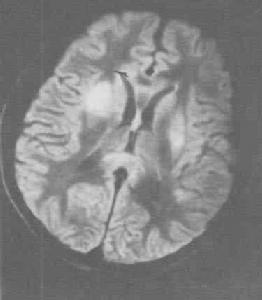

正常大腦結構精神活動異常是各類精神障礙重要標誌之一。精神障礙累及個體的基本心理過程,表現出繁多的精神病理現象。精神障礙時常表現在認知、情感和意志活動等幾個環節之中,有時也會涉及到注意、記憶和智慧型。識別和掌握精神病理特徵目前仍然是研討各類精神障礙的診治規律的重要方法。精神症狀也可按精神活動的過程來分類。

腦梗塞器質性精神障礙是一組由腦部疾病或軀體疾病導致的精神障礙。由腦部疾病導致的精神障礙,包括腦變性疾病、腦血管病、顱內感染、腦外傷、腦瘤等所致精神障礙。軀體疾病導致的精神障礙只是原發軀體疾病症狀的組成部分,也可與感染、中毒性精神障礙統稱為症狀性精神障礙。一般常見類型有: